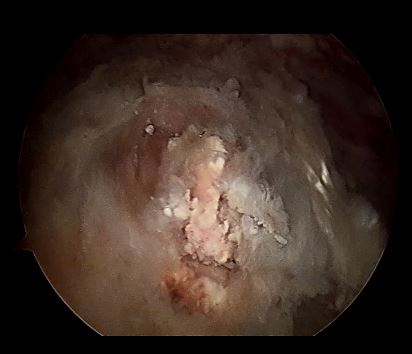

关节镜可以看见钙化灶有不同的表现,并在不同肌腱位置出现,手术中应该仔细寻找病变位置!

关节镜下钙化灶为石灰粉样、牙膏样

石膏样钙化灶

牙膏样钙化灶

钙化灶为团块状